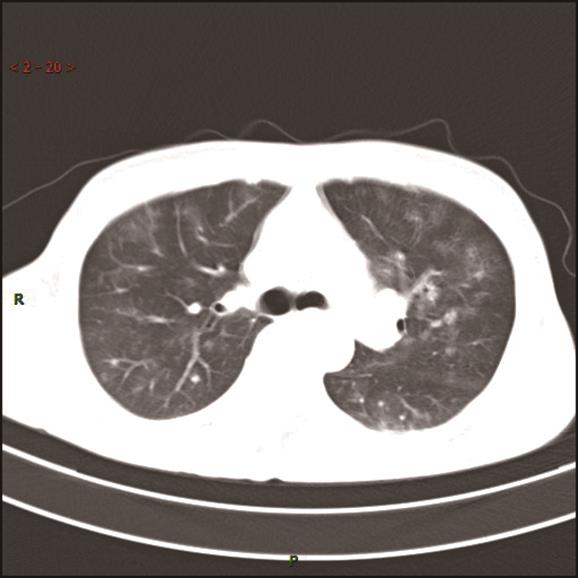

• 基于宏基因组二代测序诊断15例鹦鹉热衣原体肺炎临床特征与诊治分析

2023, 48(6):715-720. DOI: 10.13406/j.cnki.cyxb.003248

摘要 (49) HTML (29) PDF 858.28 K (202) 评论 (0) 收藏

摘要:目的 探讨和分析少见鹦鹉热衣原体肺炎的临床特征、诊治及预后,以期提升临床相关学科领域对该病的认识。方法 回顾性研究赣南医学院第一附属医院2017年1月至2022年12月确诊的15例鹦鹉热衣原体肺炎患者的临床资料,总结并分析该病的临床特征、诊断与鉴别要点,同时检索国内外文献资料对鹦鹉热衣原体肺炎的最新诊疗进展予以系统性讨论。结果 纳入本研究的15例鹦鹉热衣原体肺炎患者中,男性10例(66.67%),女性5例(33.33%),年龄62(32~79)岁,禽类接触史14例(93.33%),基础疾病史8例(53.3%),转化为重症肺炎5例(33.33%)。15例患者中,白细胞计数(white blood cell count,WBC)正常8例(53.3%),WBC升高5例(33.3%),WBC减低2例(13.3%);血红蛋白(hemoglobin,HGB)正常9例(60.0%),减低6例(40.0%);中性粒细胞百分比(neutrophils,NE)升高13例(86.7%);所有患者(100.0%)C反应蛋白(C-reactive protein,CRP)均显著升高;13例(86.67%)患者降钙素原(procalcitonin,PCT)升高;12例(80.0%)患者乳酸脱氢酶(lactate dehydrogenase,LDH)升高;11例(73.33%)肝功能异常;8例(53.33%)肾功能异常;6例(40.0%)凝血功能异常;13例(86.7%)电解质紊乱。此外,11例(73.33%)患者动脉血气分析显示不同程度血氧分压降低,8例(53.33%)氧合指数(oxygenation index,OI)低于300 mmHg,4例(26.67%)患者无明显呼吸困难,未进行动脉血气分析检查。本研究所有患者均已完善经支气管镜检查,并获取支气管肺泡灌洗液(bronchoalverolar lavage fluid,BALF)行宏基因组二代测序(metagenomic next-generation sequencing,mNGS)检测,检出的病原体除鹦鹉热衣原体外,所有患者均合并多种病原体感染。15例患者均已完善肺部电子计算机断层扫描(computed tomography,CT)等影像学检查,单侧肺部实变7例(46.67%),双侧实变8例(53.33%);9例(60.0%)患者伴有胸腔积液,部分患者可以表现出多种影像学表现,包括实变影、磨玻璃影、团块样实变影、反晕征、纵隔和肺门淋巴结肿大等。15例鹦鹉热衣原体肺炎患者在确诊后均予规范抗感染治疗,其中5例重症肺炎患者中2例患者予体外膜肺氧合(extracorporeal membrane oxygenation,ECMO)辅助治疗,所有患者均未见治疗相关不良反应或不良事件,平均住院日为13.9 d。本研究所有患者未见死亡,均好转出院。结论 鹦鹉热衣原体肺炎临床特征及表现缺乏特异性,易出现重症化,经支气管肺泡灌洗液予mNGS检测可精准确诊,早期予四环素类及喹诺酮类抗生素可最大程度改善患者预后。

• 0+1

• 1+1

• 2+1

• 3+1